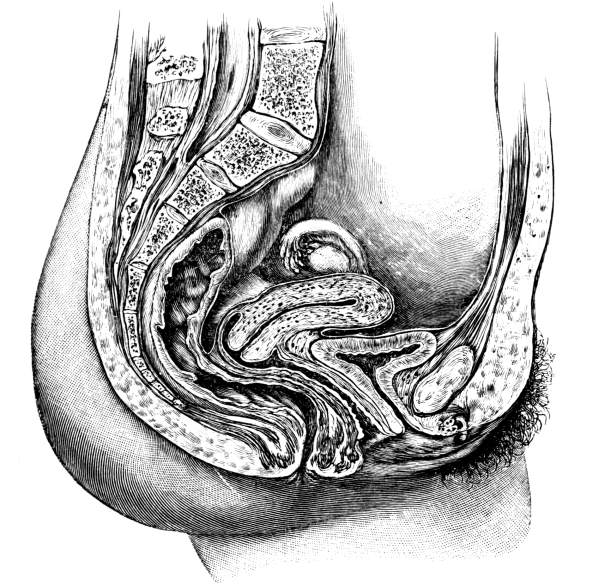

| The Pelvis and the Genital Organs | 161 |

The Pelvis, 161—The Male Generative Organs, 164—The Prostate Gland, 164—The Testes, 165—The Penis, 165—The Female Generative Organs, 165—The Ovaries, 165—The Fallopian Tubes, 166—The Uterus, 167—The Vagina, 168—The External Genitalia in the Female, 169—The Vulva, 169—The Mons Veneris, 169—The Labia Majora, 169—The Labia Minora, 170—The Clitoris, 170—The Meatus Urinarius, 170—The Hymen, 170—The Fourchette, 170—The Perineal Body, 170—The Perineum, 170. |